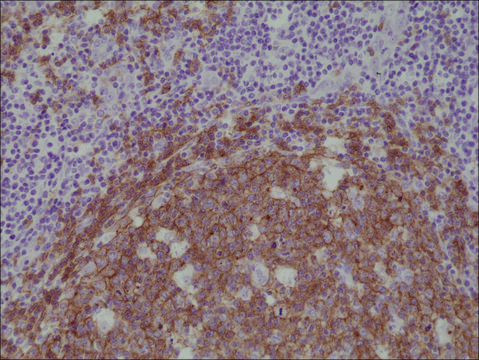

Anti-CD19 antibody, Rabbit monoclonal recombinant, expressed in HEK 293 cells, clone RM332, purified immunoglobulin

Anti-CD19 antibody, Rabbit monoclonal